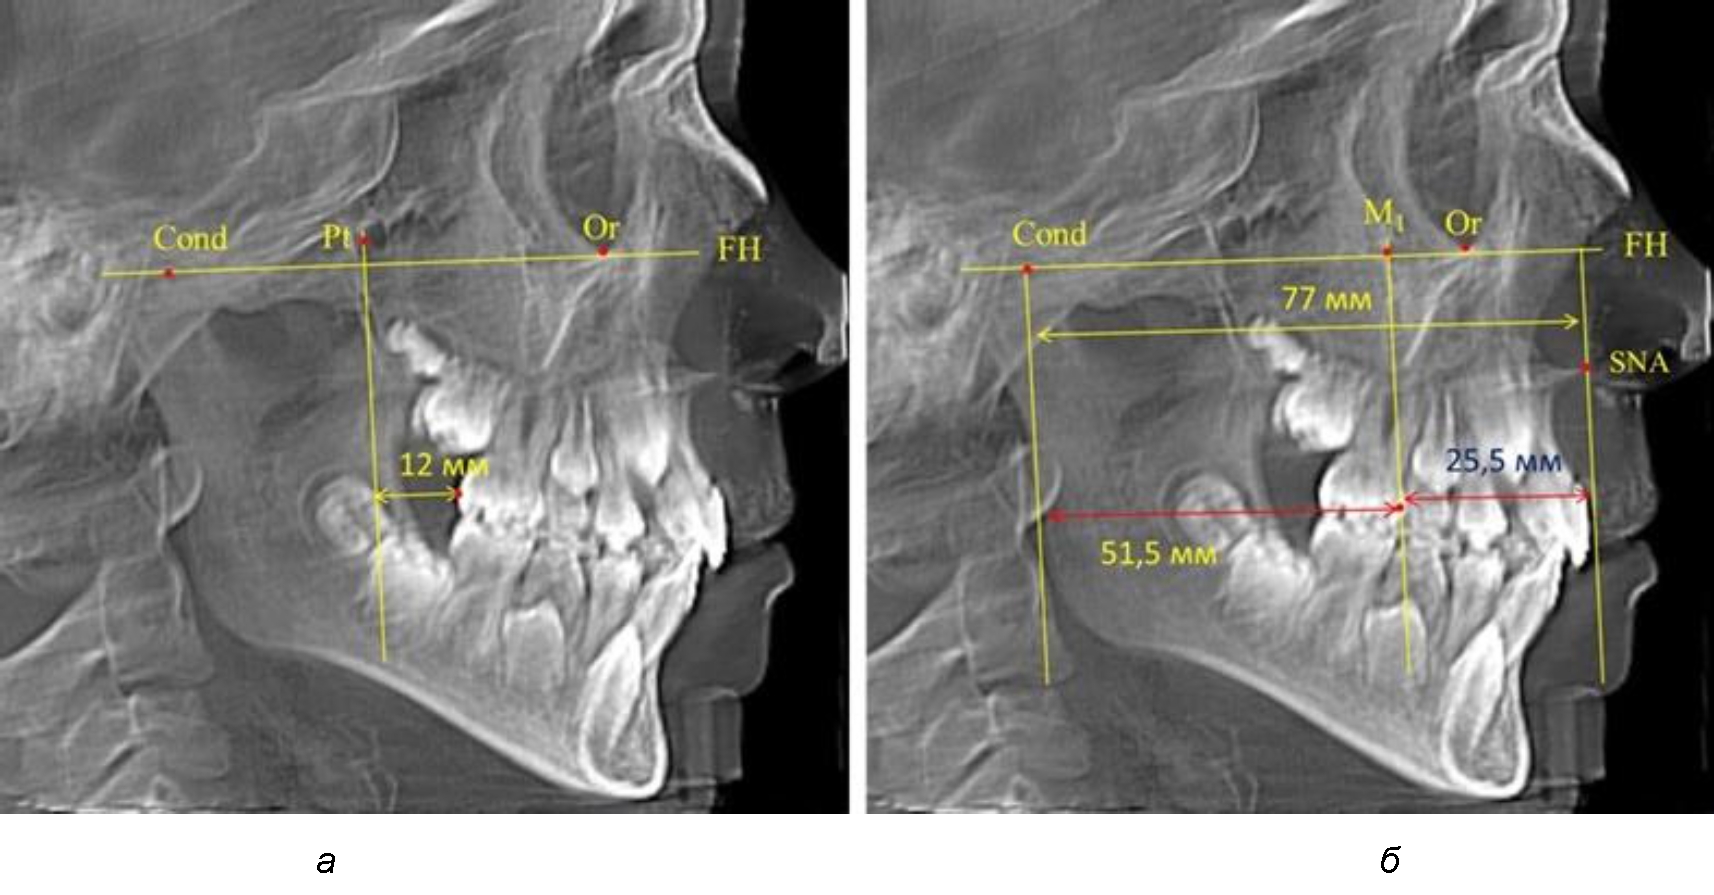

В то же время при увеличенном расстоянии от крыловидной вертикальной плоскости PTV до дистальной поверхности верхнего первого постоянного моляра, равное 23 мм, сагиттальный размер гнатического отдела составил 92 мм. При этом отношение кондилярно-спинального расстояния к кондилярно-молярному размеру (30,5), так же, как и при малых размерах, было близким к коэффициенту 1,5, что представлено на рис. 3.

Рис. 3. Особенности положения первых моляров по R. E. McDonald (а) и по предложенному методу (б) при увеличенном молярно-крыловидном расстоянии

По мере роста челюстей увеличивалась глубина гнатического отдела лица, и кондиллярно-спинальный размер составлял в среднем (74,57 ± 0,93) мм. Дистальная поверхность первого постоянного моляра отстояла от крыловидной вертикали на величину, составляющую около 11 мм, что, так же, как и в периоде прикуса молочных зубов, было близким по значению к данным R. E. McDonald, а именно возраст, плюс 3 мм. Однако величина ошибки среднего значения свидетельствовала о вариабельности признака даже в восьмилетнем возрасте после замены передней группы зубов и установки ключевых постоянных моляров в окклюзионное равновесие. Обращает на себя внимание отношение глубины гнатического отдела лица к дистальному отделу, а именно к кондилярно-молярному расстоянию (рис. 5).